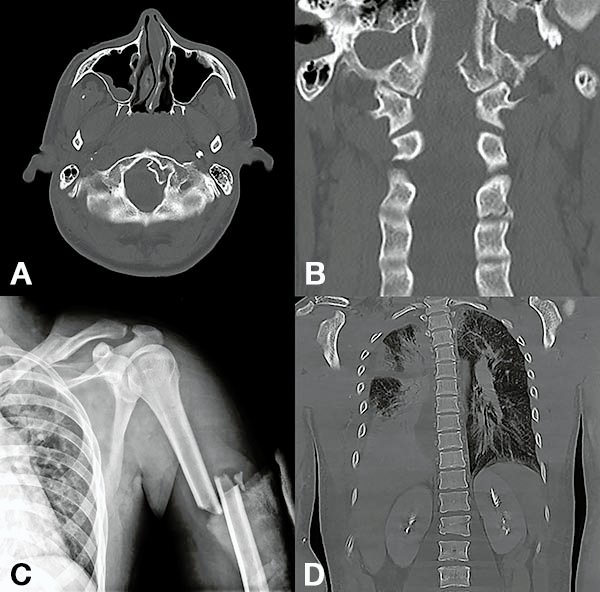

Figura 1:

Caso 24. Hombre 21 años con politraumatismo por accidente vial. A y B: Fractura del cóndilo occipital izquierdo. C: Fractura expuesta del húmero izquierdo y clavícula. D: Contusión pulmonar más hemotórax derecho.